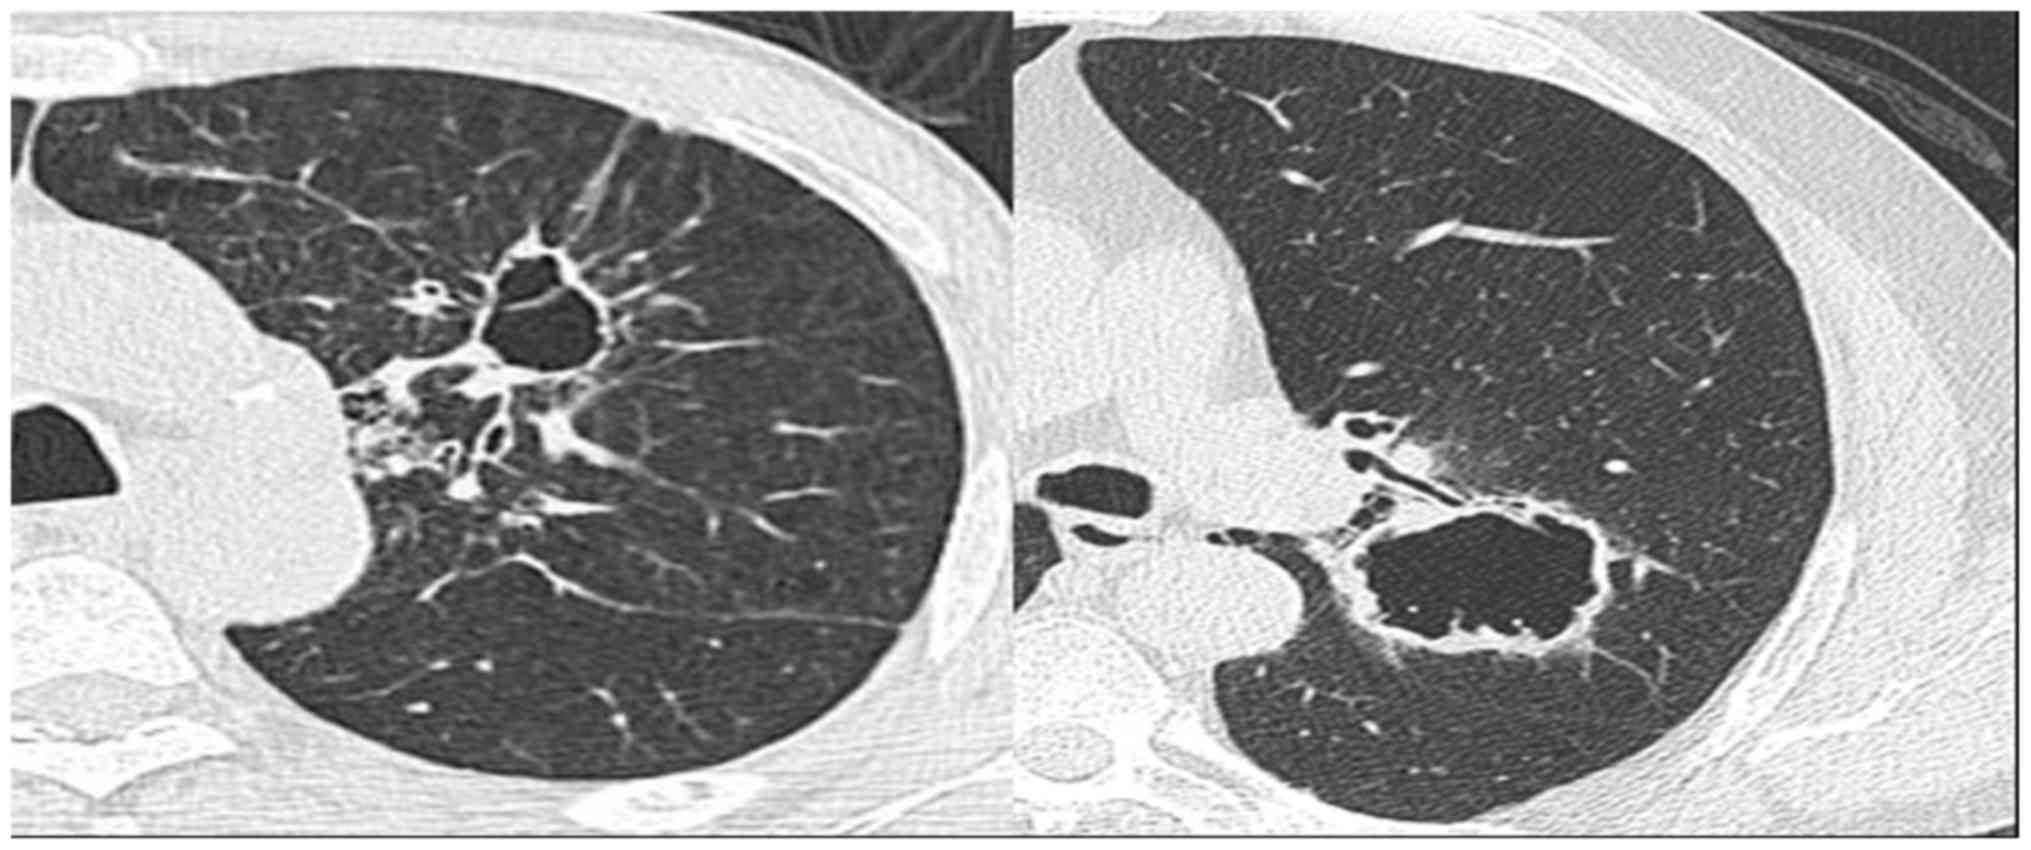

A cystic lesion was identified in the right upper lung of a 51-year-old patient, who had a long history of smoking and occasional bloody sputum, when he was admitted to hospital for fracture. PET/CT revealed a highly metabolic lesion with multiple highly metabolic lymph nodes in the right hilum. Pathology revealed a poorly differentiated adenocarcinoma with multiple lymph node metastases, and the patient received Iressa (250 mg once a day). Patients were followed up since 2015. Imaging examinations revealed an increasingly smaller cyst and increasing parenchyma. In the final imaging scans, formation of a new cavity was noted (Fig. 5).